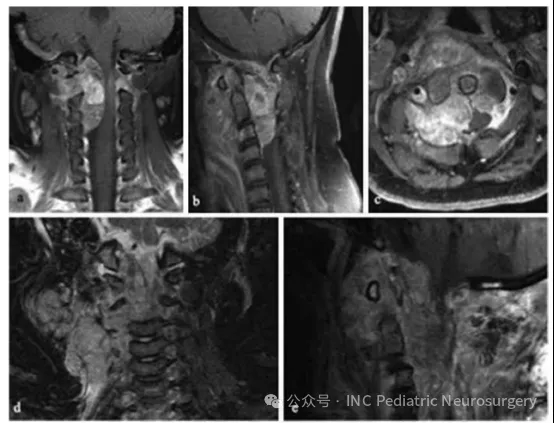

患者于2001年就诊,10岁,既往有8个月颈部疼痛和3周左上肢无力及感觉异常的病史。影像学检查发现C1-C3节段脊索瘤(图5)。患者首先行经口活检/部分减压术。病理诊断为不典型组织学类型,随后接受两个周期ICE方案化疗。

活检后40天,患者接受经后正中入路的部分肿瘤切除术,行C1-C3椎板切除及髂骨植骨融合术。术后,患者进一步接受姑息性放疗(在重症监护室期间完成5次分次放疗)及27天低剂量依托泊苷化疗。

然而,肿瘤快速进展,侵犯颈椎及右侧前外方颈部软组织。确诊后4个月决定采取姑息治疗,此后不久患儿去世。

图5. 患者6 C1-C3节段脊索瘤影像资料

(a)术前冠状位T1加权增强MRI;

(b)术前矢状位T1加权增强MRI;

(c)术前轴位T1加权增强MRI;

(d)术后4个月冠状位T1加权增强MRI;

(e)术后4个月矢状位T1加权增强MRI。